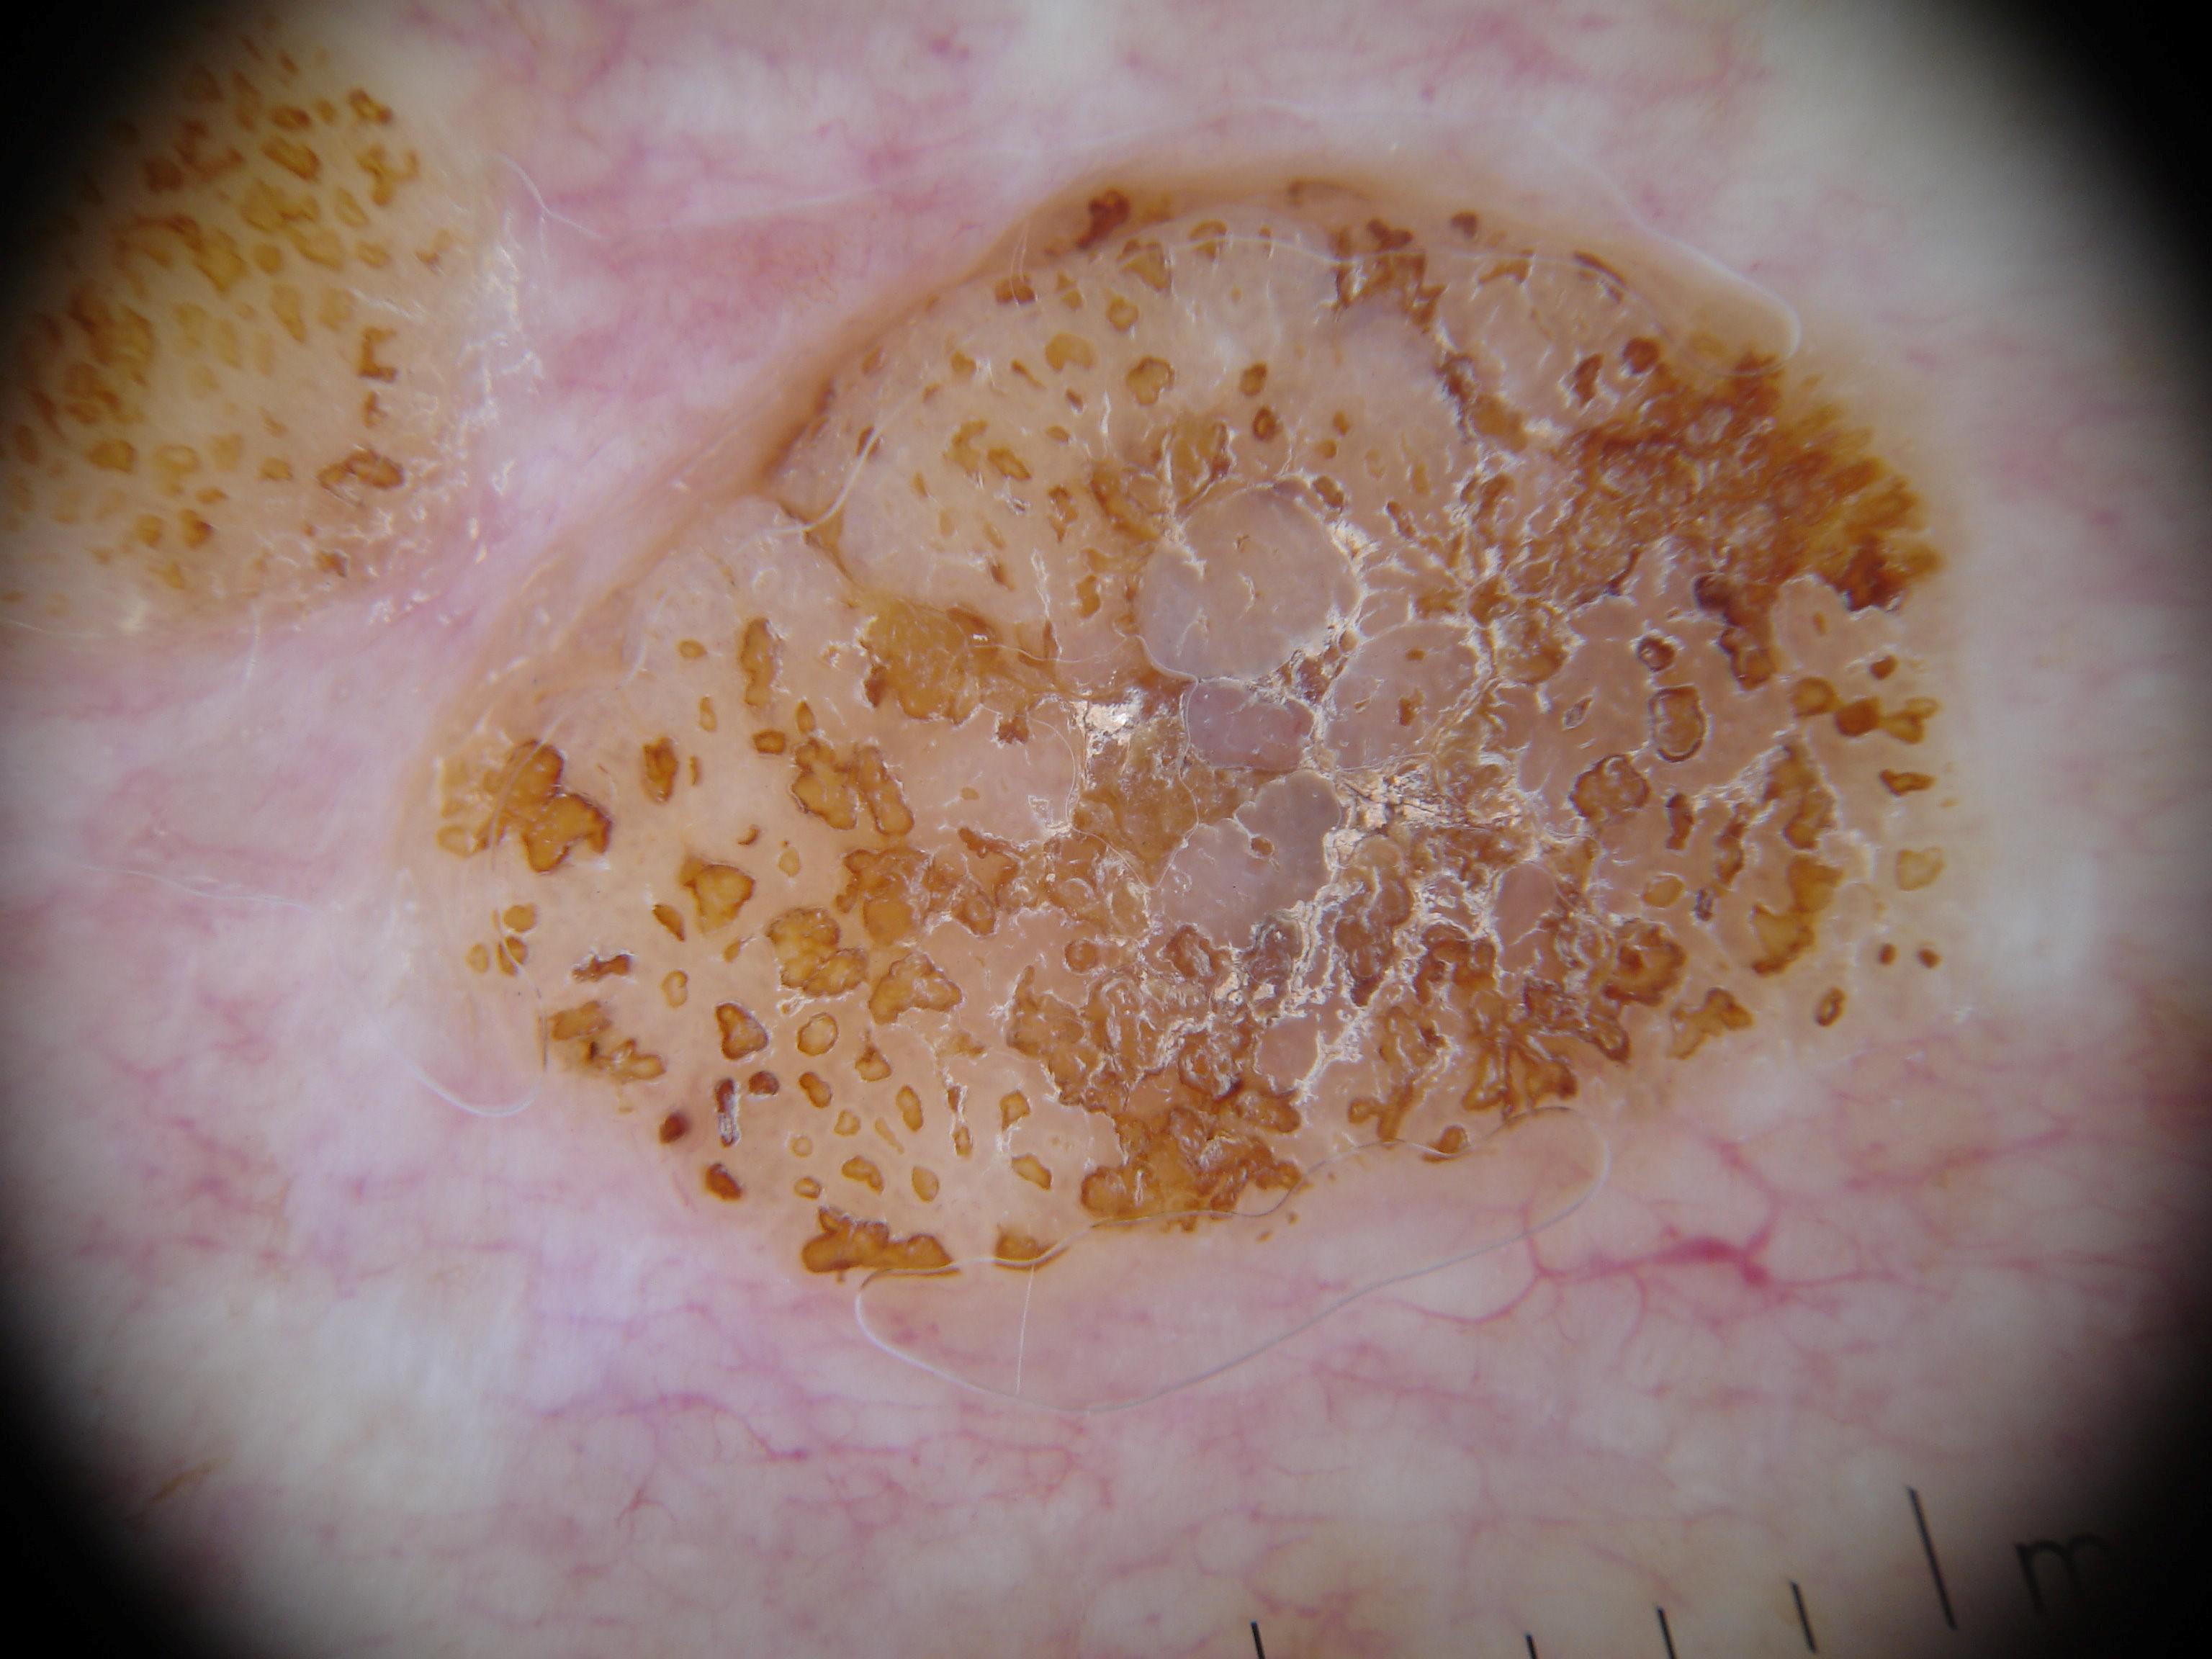

{

"age_approx": 75,

"anatom_site_general": "head/neck",

"concomitant_biopsy": true,

"dermoscopic_type": "contact non-polarized",

"diagnosis_1": "Benign",

"diagnosis_2": "Benign epidermal proliferations",

"diagnosis_3": "Lichen planus like keratosis",

"diagnosis_confirm_type": "histopathology",

"family_hx_mm": false,

"image_type": "dermoscopic",

"melanocytic": false,

"patient_id": "IP_6771437",

"personal_hx_mm": false,

"sex": "female"